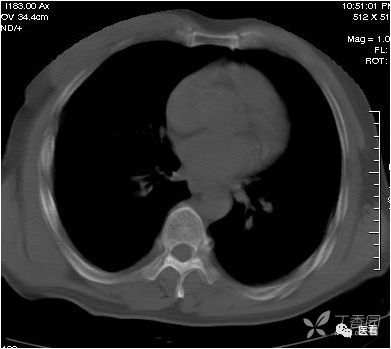

本例因为躁动明显,产生的伪影显著、杂乱。

CT造影中可能出现的假象——涡流

这里强调一个CT造影中可能产生的假象——涡流

也就是团注(高压注射器快速注入)的碘对比剂与血液没有混匀之前,没有对比剂的血液呈低密度(红箭头),有对比剂的血流呈高密度,不要误认为是血栓